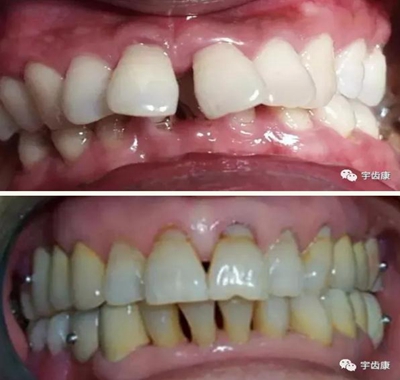

7. 共同就位道的調(diào)節(jié)

8. 實(shí)際備牙產(chǎn)生的問題

牙體預(yù)備時(shí)需注意的問題

模型檢查

模擬預(yù)備